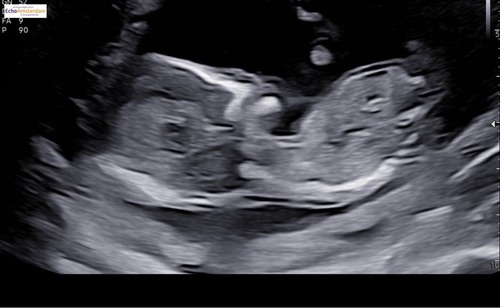

Iemand een idee wat het zou zijn?🩷💙 op deze echo was ik 15+2🤗

Ik denk een jongen